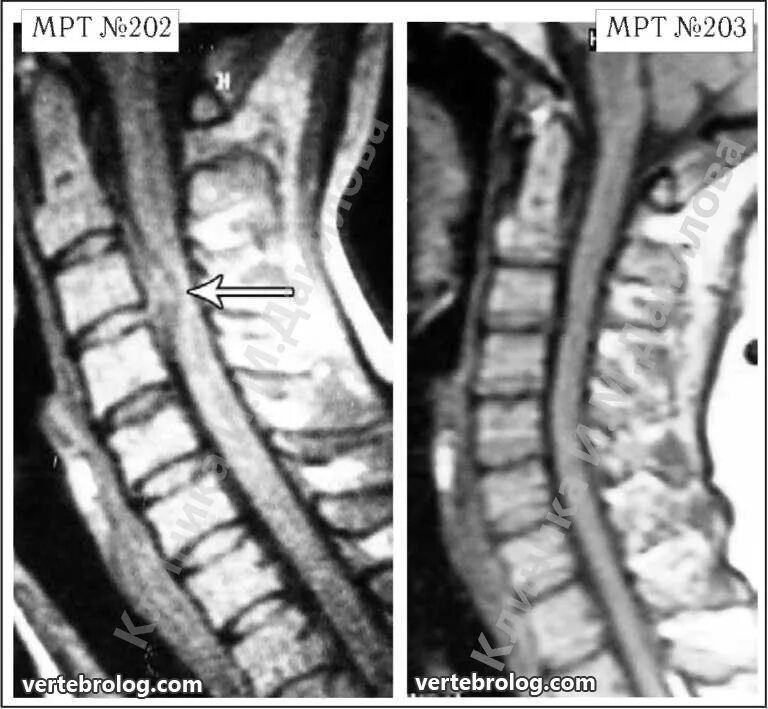

Каудальная миграция грыжи диска